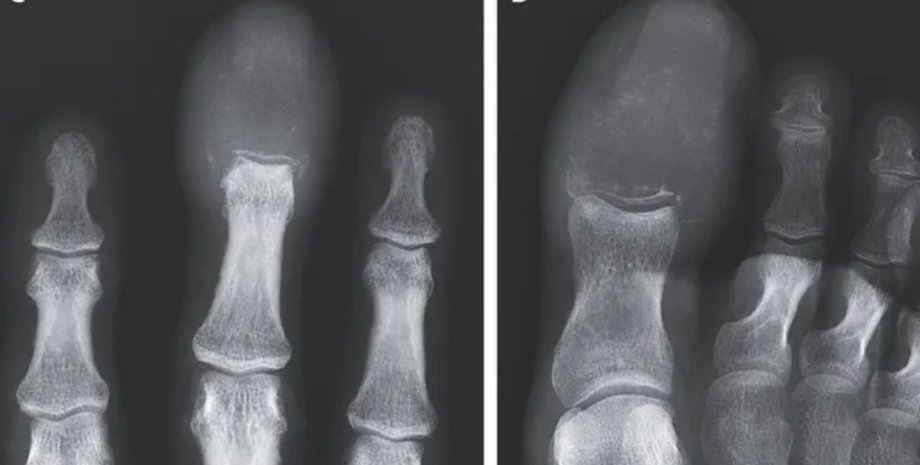

Фото: The New England Journal of Medicine ©2025.

Во время обследования пациента врачи обнаружили, что кончики опухших пальцев были на ощупь плотными и покрасневшими. Дальнейшее сканирование показало, что раковая опухоль полностью заменила кости в пальцах руки и ноги мужчины. Речь идет о литических поражениях – области, где разрушается кость, оставляя отверстия или пустые пространства в скелете. Такие поражения обычно вызваны патологическим процессом, например, раком.

Давно известно, что рак, распространившийся на кости, может имитировать подагру или остеомиелит. Но рентгенография помогает поставить точный диагноз.

На основе рентгенограммы у 55-летнего пациента был диагностирован акрометастаз, который является редкой формой рака, встречающаяся ниже локтя или колена. Акрометастазы составляют лишь около 0,1% случаев распространения рака на кости.